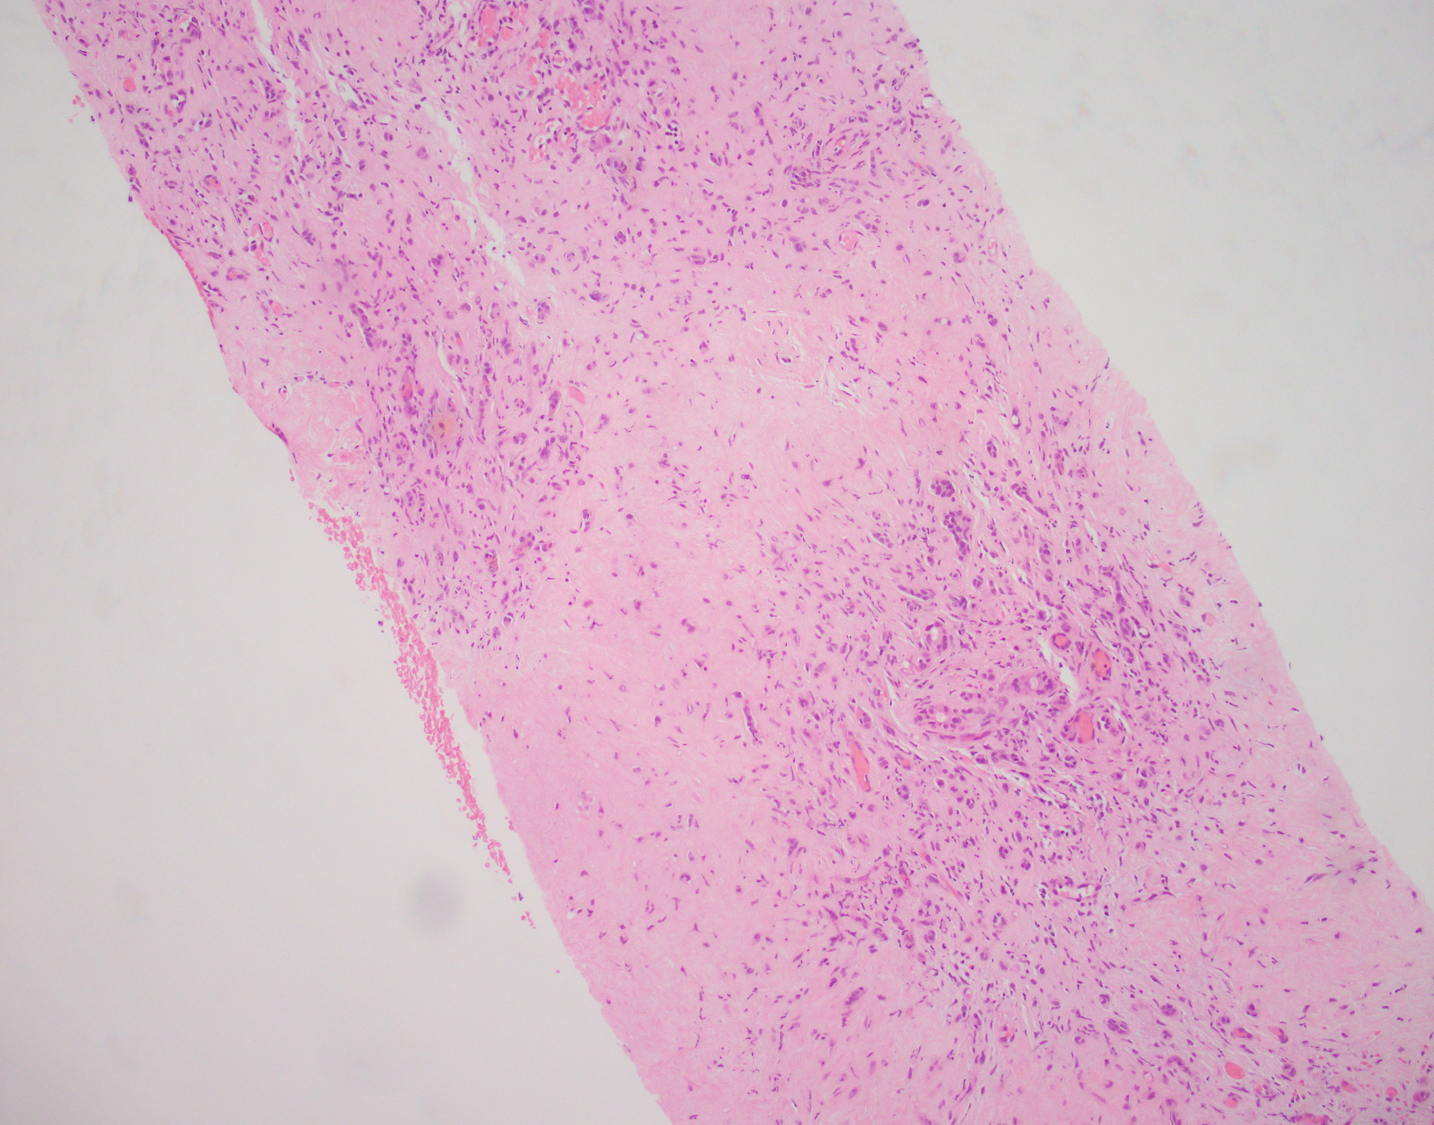

Figure 1: Hyalanized stroma with scattered cells

This tumor typically shows scattered mildly atypical cells in a background of fibromyxoid stroma. The diagnostic feature is the presence of intracytoplasmic vacuole/lumina formation. The atypical epithelioid cells are positive for ERG and CD31, supporting the vascular nature of this tumor. The differential diagnosis includes carcinoma, particularly metastatic, and angiosarcoma. Lack of marked atypia argues against the diagnosis of angiosarcoma. The keratin stain was negative in this case, which along with the positivity for vascular markers, rules out the possibility of carcinoma, though keratin positivity can be rarely seen in epithelioid vascular tumors.

Epithelioid hemangioendothelioma is a rare low-grade vascular malignancy that occurs in adults. The tumor is usually multifocal. It typically grows around pre-existing structures. Entrapped portal tract/bile duct can be seen in the tumor, as seen in this case.